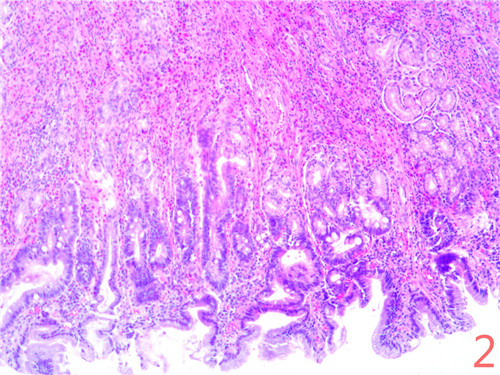

显微镜下所见:胃窦粘膜表层可见肠上皮化生,固有腺体减少,代之以假幽门腺化生,固有层内有较多淋巴细胞、嗜酸性粒细胞浸润,可深达粘膜肌内,局灶见呈巢状或腺样排列,细胞形态较一致,胞核染色质细腻的上皮样细胞(图2);免疫组化显示上述细胞CgA(图3)阳性。